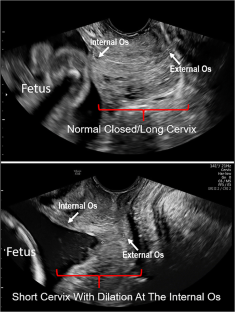

Spontaneous preterm birth (sPTB), a major cause of infant morbidity and mortality, must involve premature cervical softening/dilation for a preterm vaginal delivery to occur. Yet, the mechanism behind premature cervical softening/dilation in humans remains unclear. We previously reported the non-pregnant human cervix contains considerably more cervical smooth muscle cells (CSMC) than historically appreciated and the CSMC organization resembles a sphincter. We hypothesize that premature cervical dilation leading to sPTB may be due to (1) an inherent CSMC contractility defect resulting in sphincter failure and/or (2) altered cervical extracellular matrix (ECM) rigidity which influences CSMC contractility. To test these hypotheses, we utilized immunohistochemistry to confirm this CSMC phenotype persists in the human pregnant cervix and then assessed in vitro arrays of contractility (F:G actin ratios, PDMS pillar arrays) using primary CSMC from pregnant women with and without premature cervical failure (PCF). We show that CSMC from pregnant women with PCF do not have an inherent CSMC contractility defect but that CSMC exhibit decreased contractility when exposed to soft ECM. Given this finding, we used UPLC-ESI-MS/MS to evaluate collagen cross-link profiles in the cervical tissue from non-pregnant women with and without PCF and found that women with PCF have decreased collagen cross-link maturity ratios, which correlates to softer cervical tissue. These findings suggest having soft cervical ECM may lead to decreased CSMC contractile tone and a predisposition to sphincter laxity that contributes to sPTB. Further studies are needed to explore the interaction between cervical ECM properties and CSMC cellular behavior when investigating the pathophysiology of sPTB.